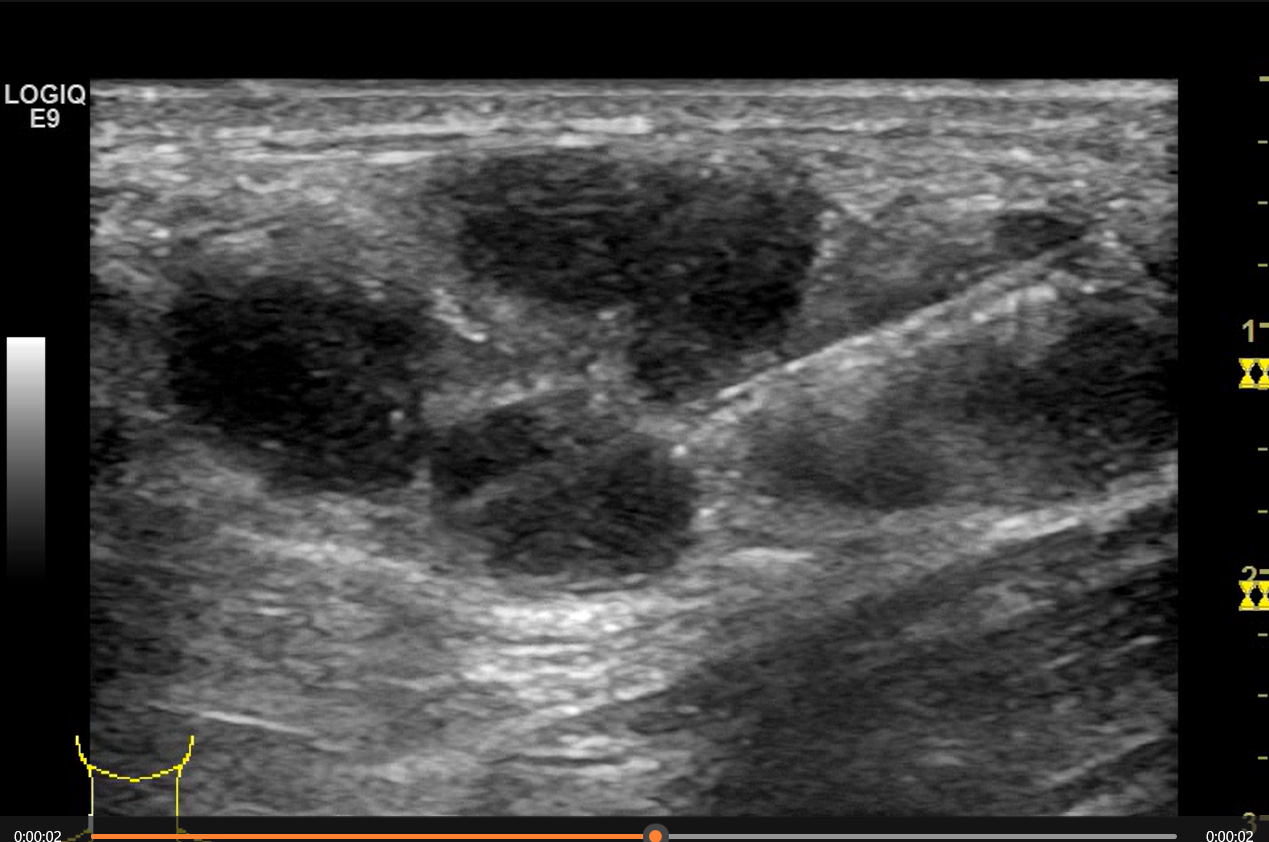

超声引导下淋巴结穿刺活检术中

术中超声实时监测图像

这两位患者中,一位是因为腋下有肿物前来我院就诊;另一位是因为颈部出现肿物想完善检查和治疗。超声检查均提示为多发淋巴结肿大。门诊医生看过超声结果后,表示可以做超声引导下穿刺活检对淋巴结肿大病因进行进一步的明确诊断,所以两位患者来到我科了解相关内容。我科介入团队医师接诊两名患者后,通过分析常规超声结果,针对淋巴结可能存在坏死灶的情况,建议患者先做超声造影。造影评估发现,淋巴结内存在多处坏死,因此在术中介入团队医师们精准地避开了淋巴结的坏死区域,在尽量减少穿刺次数避免损失的原则上取出了有意义的组织。超声介入团队的陈俏伟医师、陈钦主治医师和徐小嫣护理师在超声医学科负责人高兴副主任医师的现场指导下,成功做到了术前有效评估,术中安全疼痛感轻微,术后无并发症。